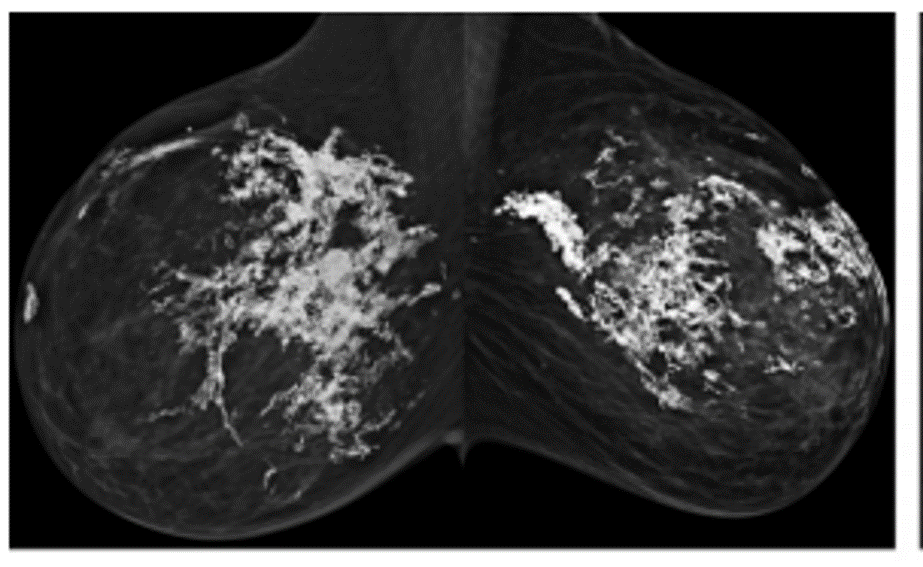

mucinous carcinoma/colloid carcinoma

-subtype of IDC

MR: Characteristic high-signal T2/STIR due to high mucin content; avid, slow rim enhancement